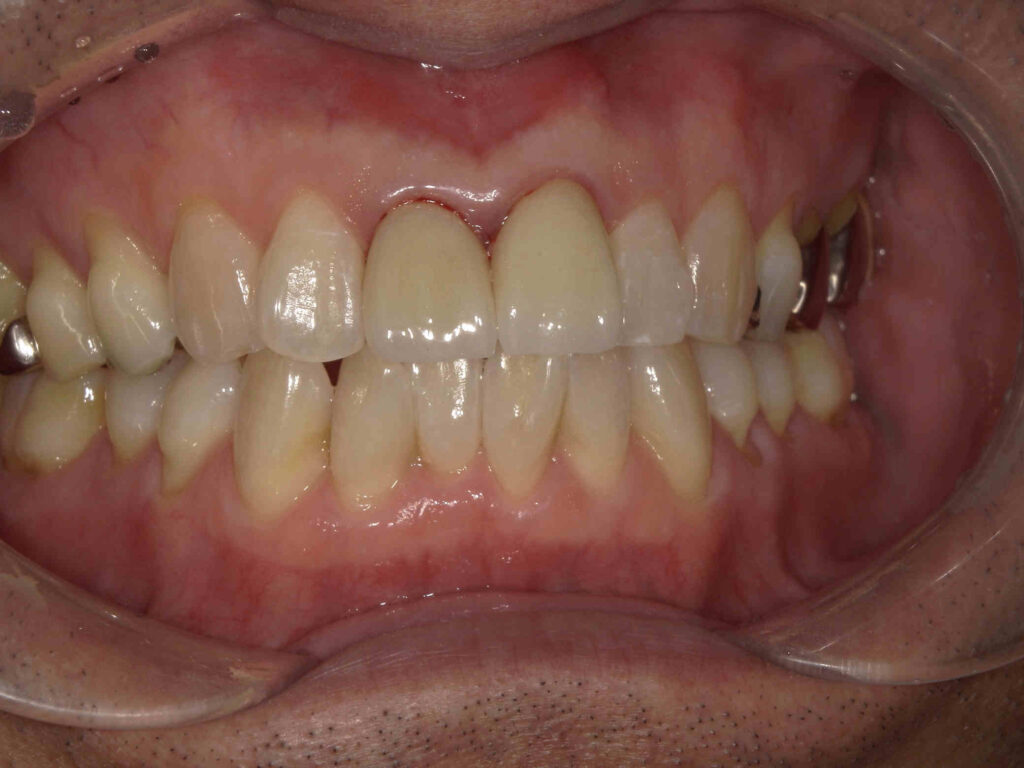

AFTER

不適合なレジン前装冠が装着されています

| 主訴 | 前歯をキレイにしたい |

|---|---|

| 診断名・ 主な症状 |

前歯部審美障害 |

| 年齢 | 40代男性 |

| 治療内容 | グラデーションジルコニアクラウン |

| 治療期間/ 通院回数 |

1カ月/2回 |

| 費用 | 242,000円 |